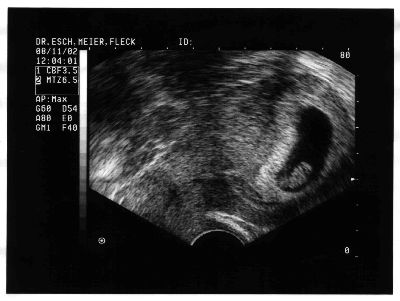

Hier das erste Bild von Pünktchen Peschel mit 12mm und 7 Wochen.